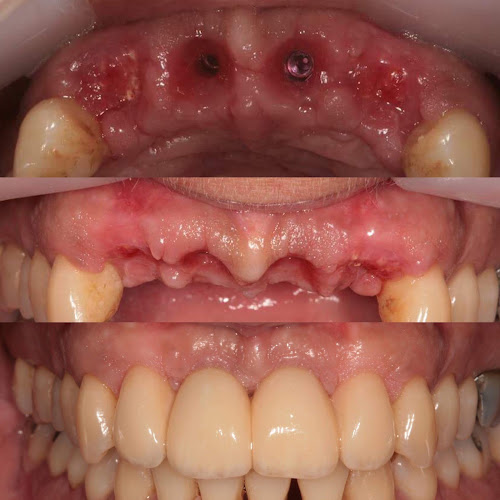

Αξιολογήσεις για Ιατρείο Περιοδοντολογίας& Εμφυτευμάτων ΓΕΩΡΓΙΟΣ Α. ΜΕΛΙΣΣΑΡΗΣ. (Οδοντίατρος) στην Χανιά (Κρήτη).